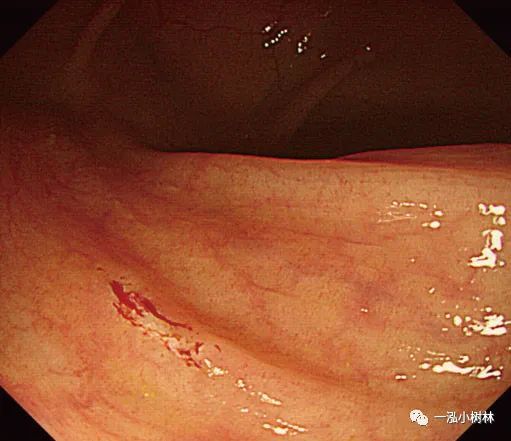

图1e 注射生理盐水下息肉切除术治疗复发性肿瘤

图1f 注射生理盐水下息肉切除术治疗复发性肿瘤